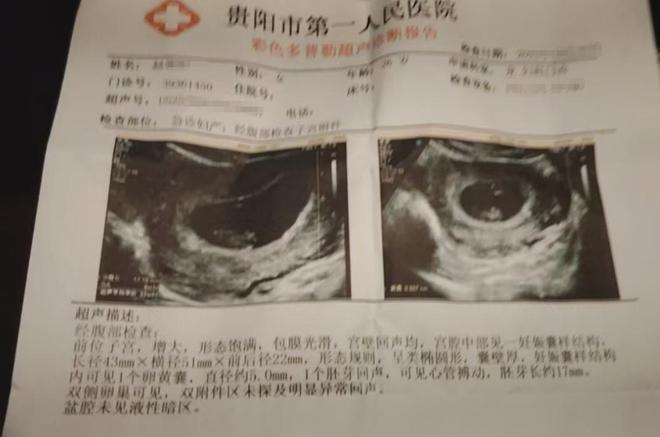

商家表示■•=,之前他们已经带着罗先生的妻子到医院进行了检查★▪,目前罗先生妻子的身体暂时无恙◆◇。虽说售卖过期产品的确是他们失责▼△▪…•,但是他们也愿意和罗先生进行沟通•◁…△■■,也提出过赔偿方案▷●▲★”麻将胡了2火锅底料过期孕,但是罗先生的★--▪□“狮子大开口◇■●▪◇”麻将胡了2★◇☆◇•,让双方的沟通陷入了僵局•□◆•。

随后▽…○▼,对方也跟着夫妇俩到医院进行了检查▷☆○。发生这个事情以后☆-◆,商家已经将过期的相关食品下架麻将胡了2麻将胡了2▼…★△△。保质期是12个月麻将胡了2☆○▷□•,也就是说这包火锅底料过期了■▷--▪★。看到记者和罗先生的到来●○…●□。

罗先生说■▽▽,虽然妻子目前没有什么明显的症状▼▽,但还不能早早地下结论○◇▼◆■。根据医生的建议◇▷▼•▽▲,罗先生的妻子后续还需要再做检查来跟进腹中胎儿的状况◁▼△●▪。可说到赔偿一事•…-,罗先生和超市负责人没有协商出一个结果来◇•▷。